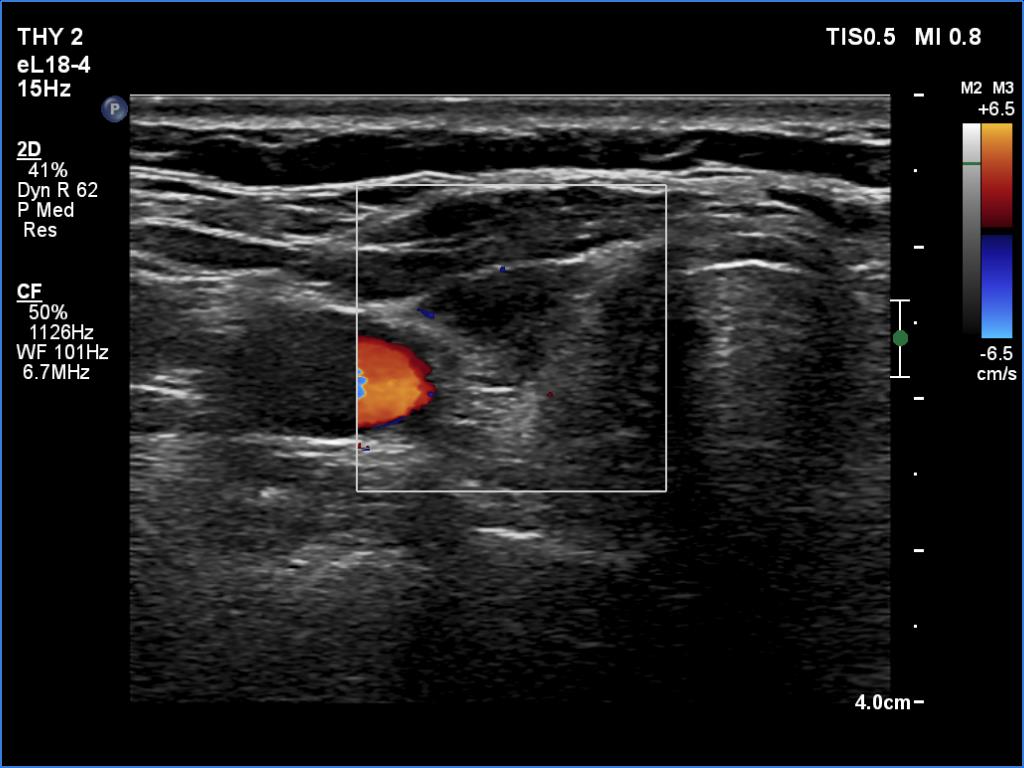

Lymphocytic thyroiditis - case 1298 (ultrasonographic picture 3)

Right lobe, longitudinal scan

Right lobe, transverse view, color Doppler mode. The lobe is avascular.